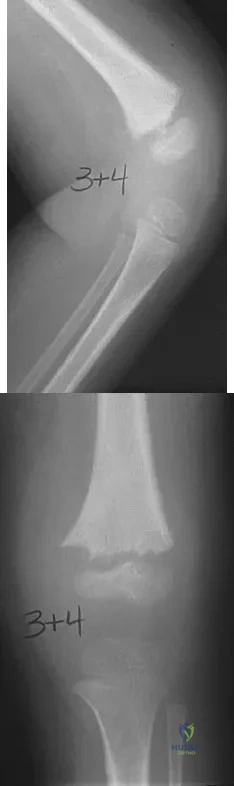

A 15-year-old girl who competes in gymnastics has immediate pain and giving way of the left elbow after falling from the uneven parallel bars and landing on her outstretched arms. Examination reveals swelling and tenderness about the elbow, especially over the medial side. Measurement of elbow motion shows 0 degrees to 125 degrees of flexion, and valgus stress at the elbow is painful. AP, lateral, and stress radiographs are shown in Figures 9a through 9c. Management should consist of

Explanation